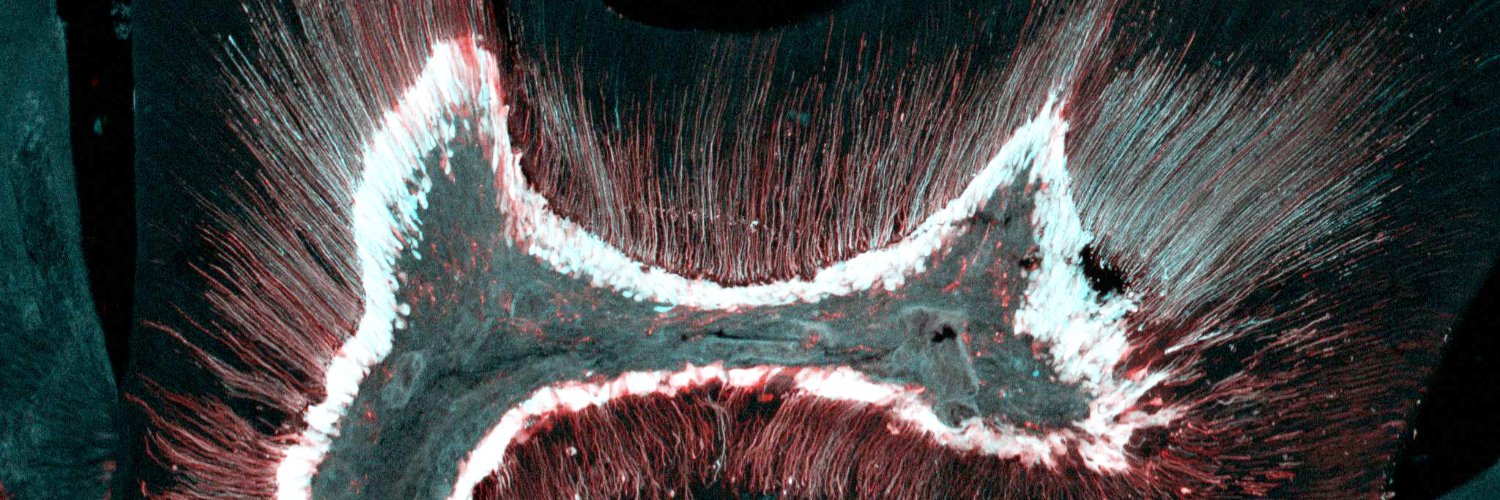

Tooth Morphogenesis and Differentiation รีทวีตแล้ว